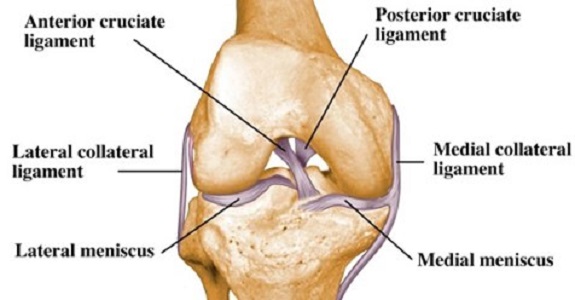

In the #exam_room, OR, or the #research_lab, these are some of the top sports #knee_surgeons in #North_America. We sought out leading sports #medicine_surgeons. #Sports_Medicine #Orthopaedic_Center #Chicago #Occupational_Orthopedics #Indiana #Indianapolis howtorelief.com/top-rated-knee…

In the #exam_room, OR, or the #research_lab, these are some of the top sports #knee_surgeons in #North_America. We sought out leading sports #medicine_surgeons. #Sports_Medicine #Orthopaedic_Center #Chicago #Occupational_Orthopedics #Indiana #Indianapolis howtorelief.com/top-rated-knee…

In the #exam_room, OR, or the #research_lab, these are some of the top sports #knee_surgeons in #North_America. We sought out leading sports #medicine_surgeons. #Sports_Medicine #Orthopaedic_Center #Chicago #Occupational_Orthopedics #Indiana #Indianapolis howtorelief.com/top-rated-knee…